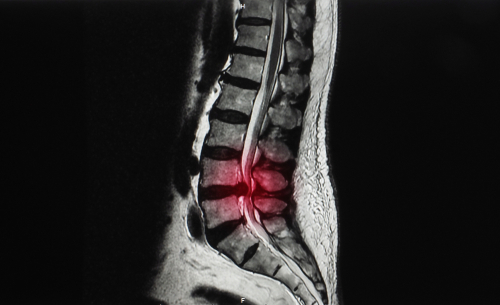

Cauda equina syndrome is a condition that occurs when the bundle of nerves below the end of the spinal cord, known as the cauda equina, is damaged. ‘Red flags’ is a commonly used term for symptoms that occur during the onset of cauda equina syndrome. If red flag symptoms are present, time is of the essence to undergo an MRI scan and surgery to release the compression of the nerves.

Miss Watson was taken by her mum to A&E after becoming increasingly concerned. At A&E, it was quickly recognised that she was suffering from cauda equina syndrome. She had an MRI scan, which confirmed a large disc protrusion compressing her cauda equina nerves. She was kept nil by mouth and placed on the emergency list for surgery.